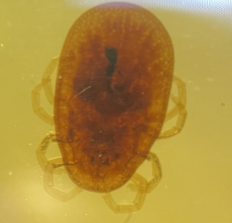

Soft tick (Ornithodorus)